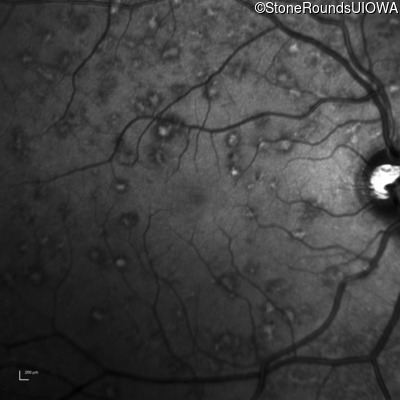

Infrared Fundus Photograph - Right - 20/15 -1 sc

Exemplar